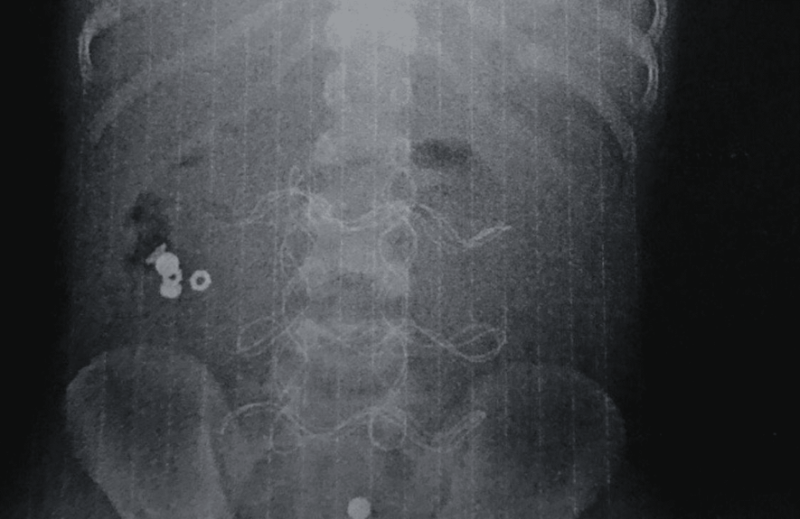

“Поділюся з вами медично складною історією з, на щастя, хорошим кінцем. До нас в ОДКЛ привезли 7-річного хлопчика у вкрай тяжкому стані інфекційно-токсичного шоку з клінікою розлитого перитоніту.

Як виявилось, все через батарейку, яку дитина проковтнула, що спричинило перфорацію тонкого кишківника”, – зазначив Тарас Мельник.

Хлопчику з Прикарпаття провели 3 операції, щоб врятувати після того, як він проковтнув батарейки

7-річний хлопчик пережив три серйозні операції та провів у лікарні 20 діб, після чого у задовільному стані його виписали додому.